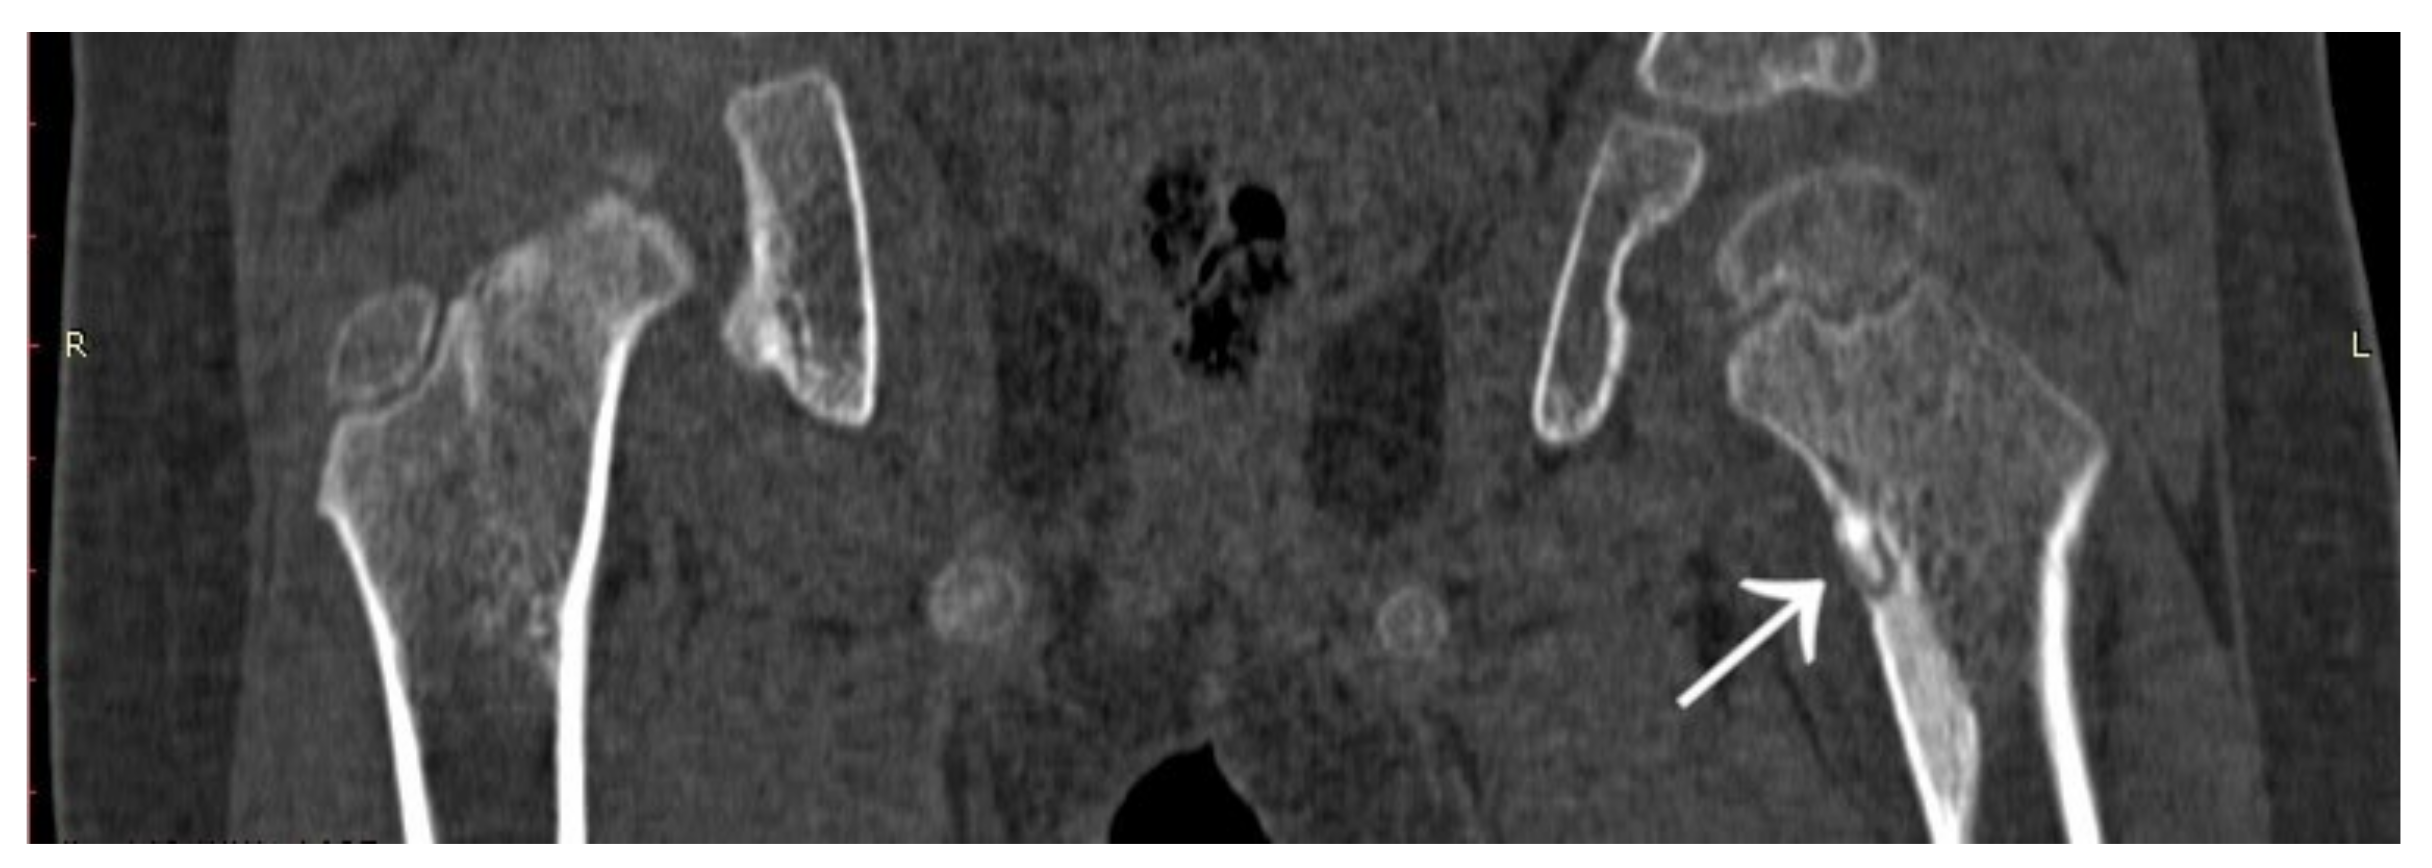

3.4. Case 4: OO Masking as a Fatigue Fracture

3.6. Case 6: OO Masking as Chronic Hip Arthritis

4. Atypical Osteoid Osteomas: Presentation and Diagnosis